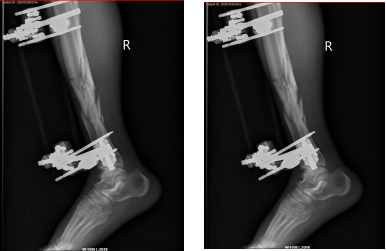

67岁的戎先生在家中不慎摔伤,致右胫腓骨开放性粉碎性骨折。

外固定支架创伤小更有利于术后恢复,对于开放性骨折或感染无法第一时间进行内固定的患者,外固定支架无异于最优选择,外固定支架已广泛应用于治疗骨折、矫治骨与关节畸形和肢体组织延长。